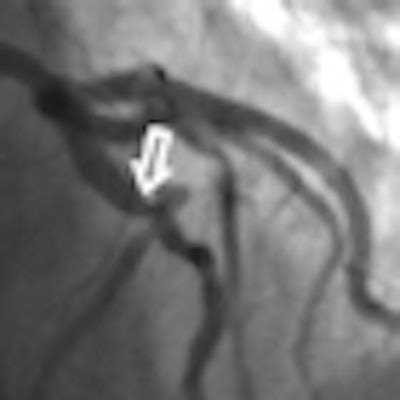

Coronary CTA found six segments and two patients with stenoses of 50% or greater that had been missed on initial angiography. The diagnostic accuracy between the tests was not significantly different (p = 0.87).

"Catheter angiography is a good gold standard, but it may not be the best because of limitations this test has which we all know about," Schoepf said. For one thing, angiography has trouble depicting a key coronary artery, the left main, because it's typically tortuous and complex anatomy is not well-suited to catheterization.

A current article in Circulation describes problems with the projection angles in catheter angiography, Schoepf said. Depending on the angle, a minor slit stenosis can appear quite significant at angiography, leading to false positives and potentially needless intervention.

"If you take vertical projection images of that it may look perfectly fine, but if you're angulated by 90°, you see a significant stenosis all of the sudden," he said.